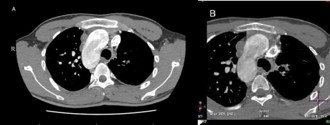

CT angiogram of chest shows complex cardiac disease including right-sided aortic arch (Figure 1), ventricular septal defect and overriding aorta (Figure 2). Non-visualization of the pulmonary trunk (Figure 3).

Figure 1: Contrast-enhanced axial CT chest at the level of the aortic arch showing right sided aortic arch.